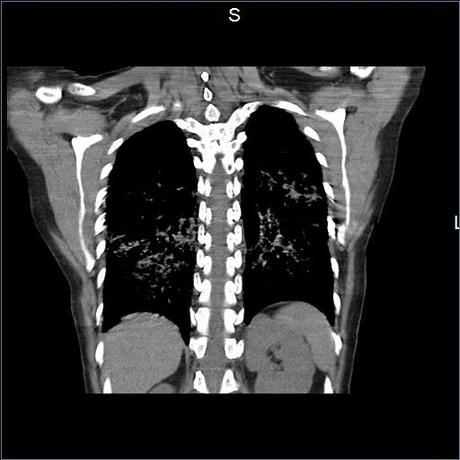

Se realiza volumen de tórax en fase simple, desde los opérculos torácicos hasta los hemidiafragmas, observándose:

El parénquima pulmonar con areas parcheadas difusas en vidrio despulido combinadas con otras areas hipodensas de baja atenuación debidas a atrapamiento aéreo y engrosamiento intersticial y zonas de fibrosis de predominio en lóbulos medios e inferiores de ambos pulmones.

- LOS HALLAZGOS PUEDEN ESTAR EN RELACIÓN A NEUMOPATIA INTERSTICIAL PROBABLE ETIOLOGIA HIPERSENSITIVA VS AUTOINMUNE/BACTERIANA/FUNGICA.